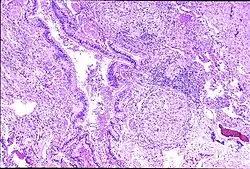

| Peribronchal non-necrotizing granuloma from berylliosis | |

Granuloma formation is seen in other diseases such as tuberculosis and sarcoidosis. Sarcoidosis, like berylliosis, also produces granulomas without a necrotic core, and so distinction between the two processes can be difficult.

Diagnosis of berylliosis is based on history of beryllium exposures, documented beryllium sensitivity, and granulomatous inflammation on lung biopsy. Given the invasive nature of a lung biopsy, diagnosis can also be based on clinical history consistent with berylliosis, abnormal chest x-ray or CT scan findings, and abnormalities in pulmonary function tests.[15]

The radiologic and pathologic features of berylliosis are very similar to sarcoidosis. Due to the strong clinical and histopathological resemblance of sarcoidosis and berylliosis, patients are sometimes misdiagnosed with sarcoidosis until the history of exposure to beryllium is elicited and beryllium hypersensitivity demonstrated with specific testing. Some studies suggest that up to 6% of all cases of sarcoidosis are actually berylliosis.[16][17]